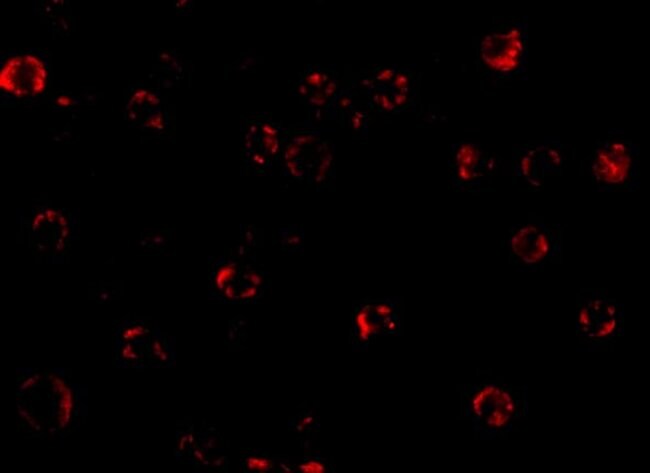

Invitrogen™ NAIP Polyclonal Antibody

Brand: Invitrogen™ PA520063

| Western Blot, Immunocytochemistry | |